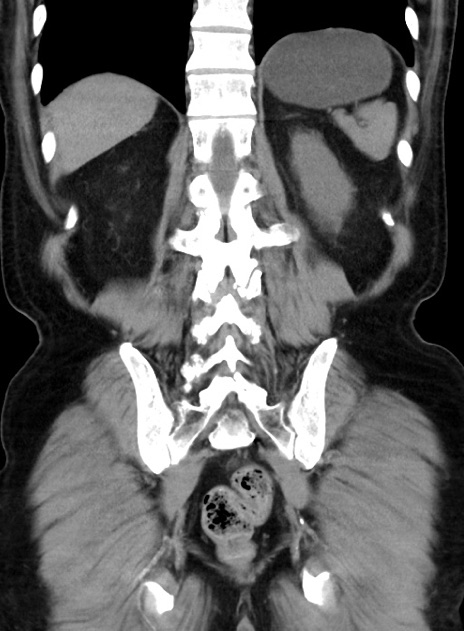

症例38(冠状断像)

【症例】70歳代 男性

【主訴】腹痛・嘔吐

【現病歴】昨晩より、嘔吐・腹痛あり。今朝になっても嘔吐あり。来院。

【既往歴】心臓バイパス手術、開腹胆摘、腸閉塞

【身体所見】BP 107/71mmHg、HR 116/min、腹部:平坦、軟、下腹部に軽度圧痛あり。反跳痛なし。

【データ】WBC 15100、CRP 0.32